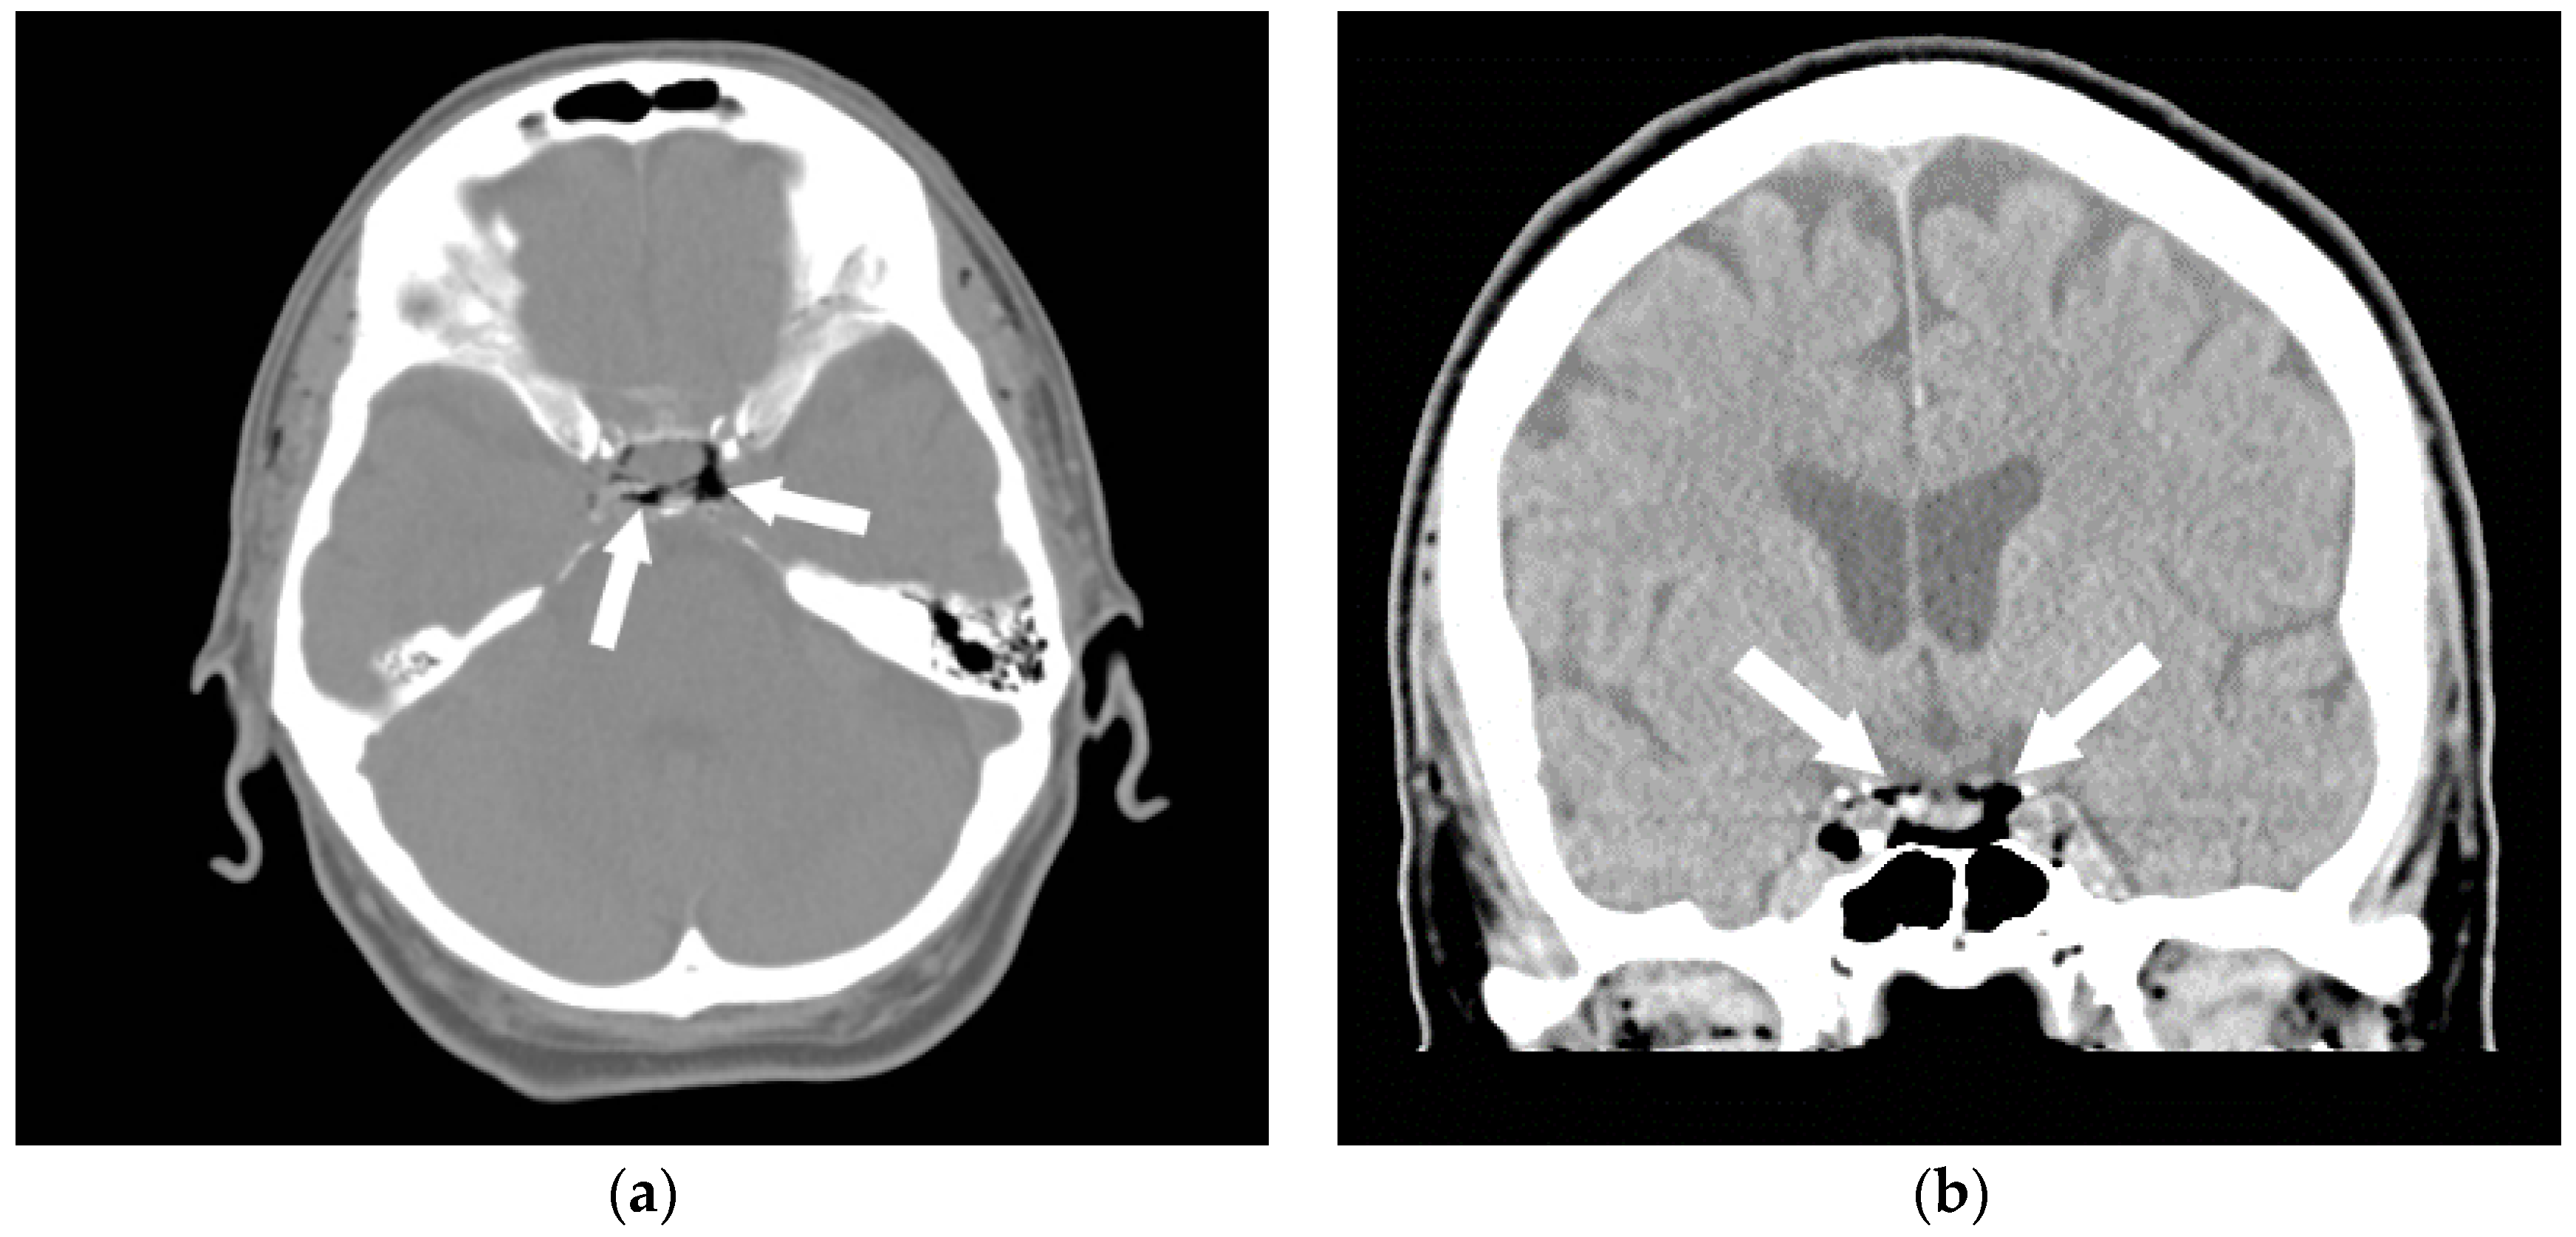

Figure 1.

A 35-year-old man was transferred from an outside hospital with altered mental status following the placement of a peripheral intravenous line. A CT of the brain was performed in the emergency room. Axial (a) and coronal (b) CT revealed a moderate amount of air in the cavernous sinuses bilaterally (arrows) as well as multiple small foci of air in the region of the pterygoid venous plexuses (c), scattered in the soft tissues and in the extradural space at the level of the upper cervical spine (arrowheads). A follow-up CT (d) was performed the next day, which revealed resolution of the previously seen air. In this case, the patient made a full recovery.